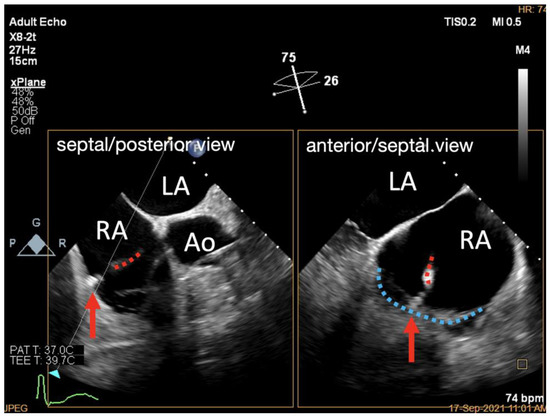

3.3. Deployment of the Tapping Screw-Shaped Anchor

3.4. Adjustment of the Clip Arm and Clamping of Annular Tissue